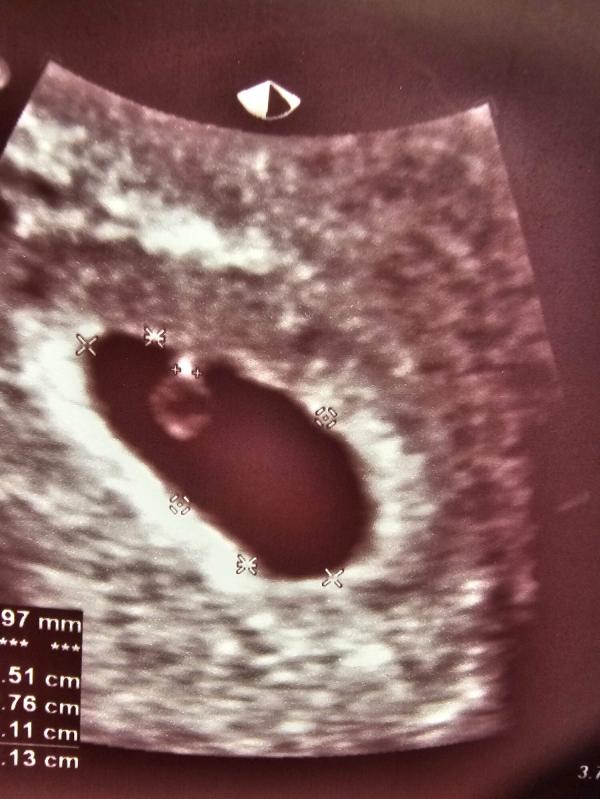

Узи 5н. 6д.

Пя 15мм

Жм 2.3мм

Ктр 1мм сердцебиение +(мерцает)

По узи все хорошо